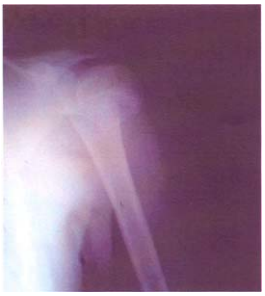

48 13 歲男童打棒球時撲壘受傷,就診時左肩痛,左臂不能抬舉,其 X 光片顯示如圖。則下列有關此傷 害之敘述,何者最正確?

①一般以外中內三分法來描述骨折 ②外觀上為斜形骨折 ③癒合不良為 常見之後遺症 ④一般分為外展形與內收形兩類 ⑤鈣化性肌炎為常見之後遺症 (A)①②③ (B)①②④ (C)②④⑤ (D)③④⑤